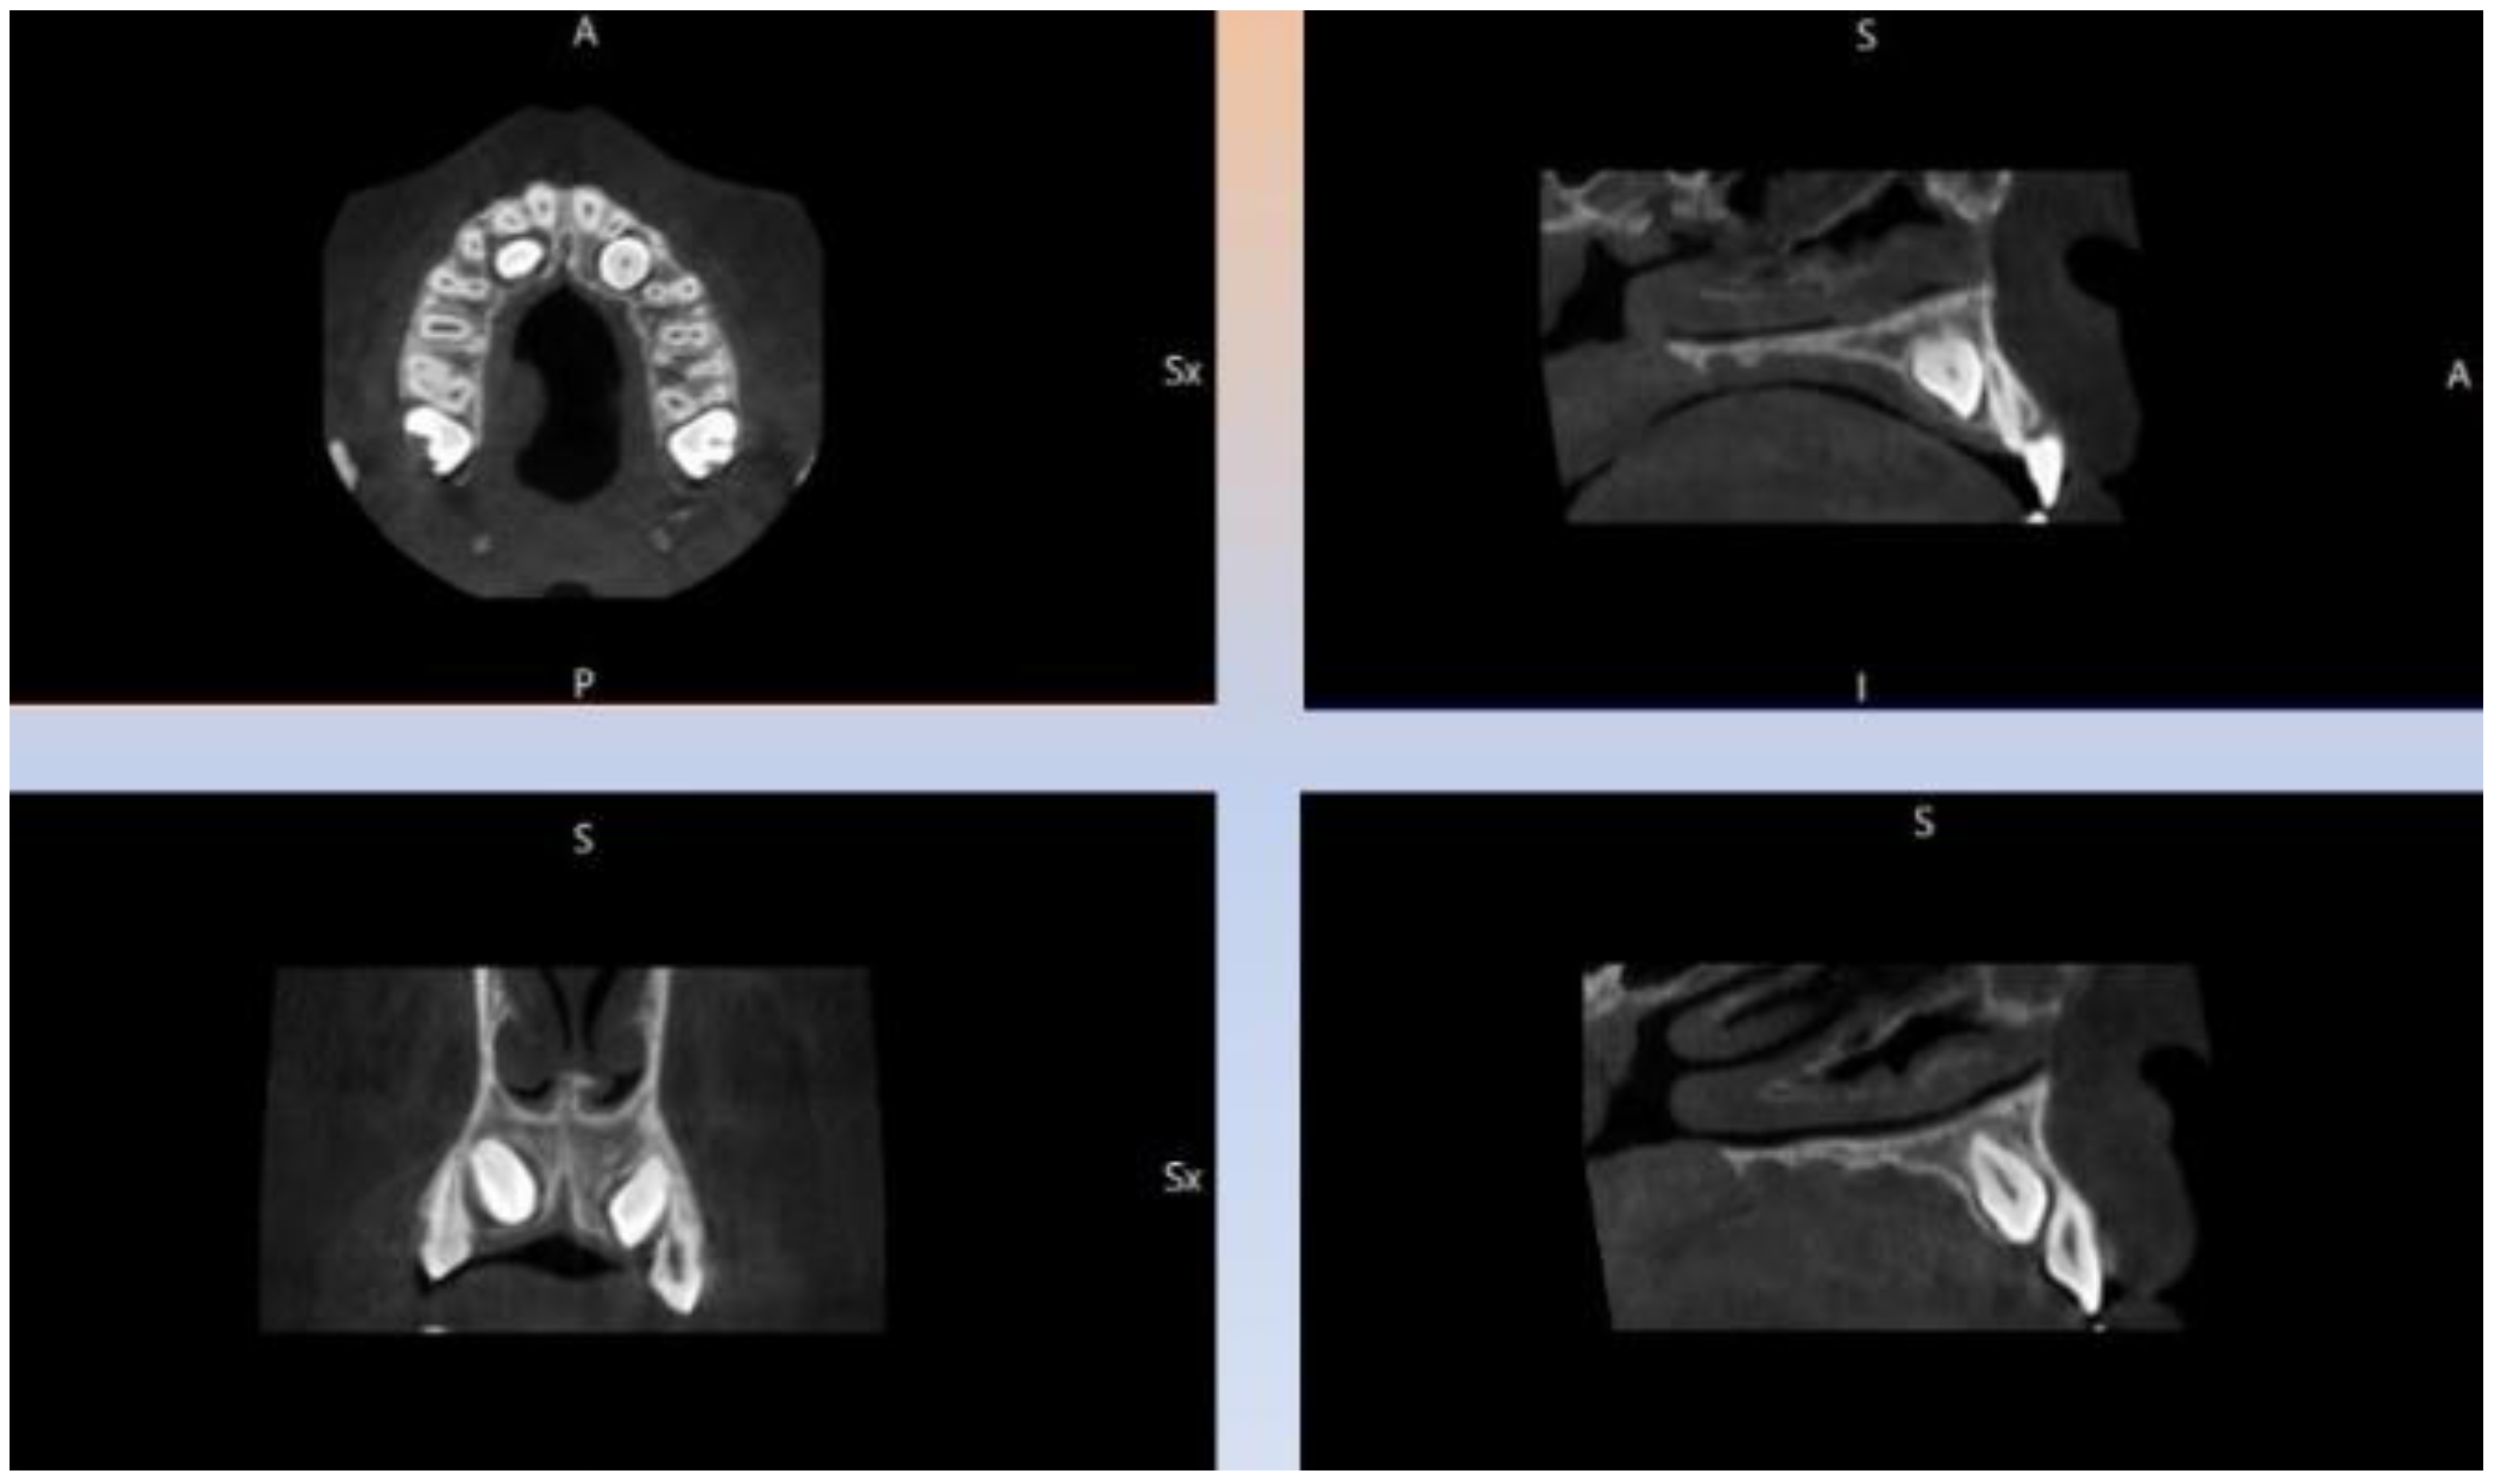

2. Case Presentation